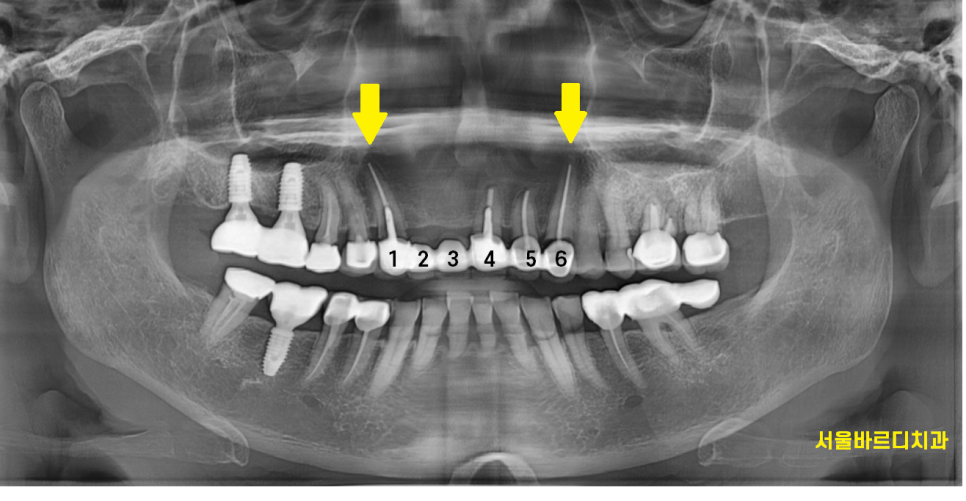

송곳니부터 송곳니까지

앞니 6개를 묶어놓은 형태로 치료를 하셨더라고요~

충치가 많이 먹은 송곳니

기둥까지 넣어 보강한 치아의 실금

양쪽 송곳니 두개 다 문제가 있었습니다.

결국 문제가 되는 치아들을 발치 후

앞니 브릿지 교체를 진행하기로 상담해드렸습니다.

하남미사치과에서 앞니 임플란트 수술을 하셨는데요.

자연치 상태에서는 4개 치아가 6개의 치아 힘을 분산했는데

앞니 브릿지 교체하면서

임플란트는 3개만 심어드렸습니다.